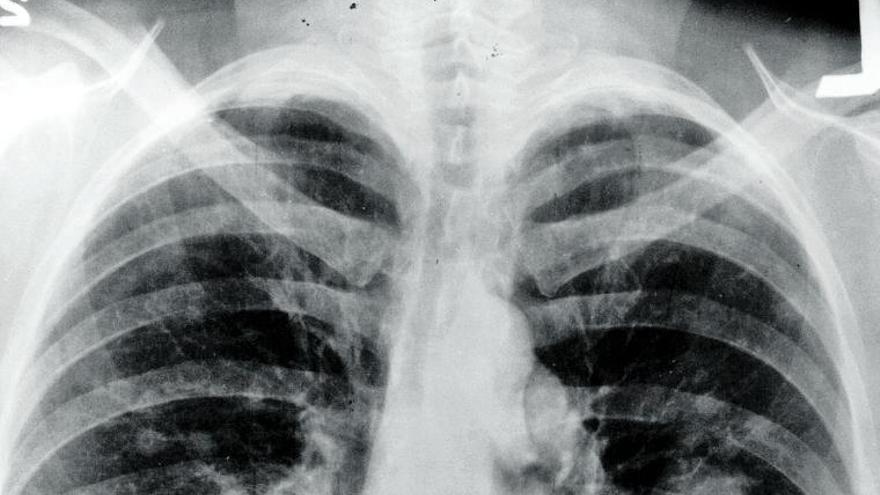

La incidencia del cáncer de pulmón es mayor entre los hombres que entre las mujeres. | L.O / marta román. málaga

Por lo tanto, actualmente y en la mayoría de los casos, el diagnóstico del cáncer de pulmón comienza en la consulta. Para ello es imprescindible valorar los síntomas y conocer los antecedentes del paciente. Con esta información, el médico valora la necesidad de completar el estudio con una serie de pruebas que comienzan por un análisis de sangre y de orina y prosigue con una radiografía de tórax; una citología de esputo, un tipo de mucosidad espesa que se produce en los pulmones; una broncoscopia o fibrobroncoscopia y una punción con aguja fina para obtener células de la lesión.